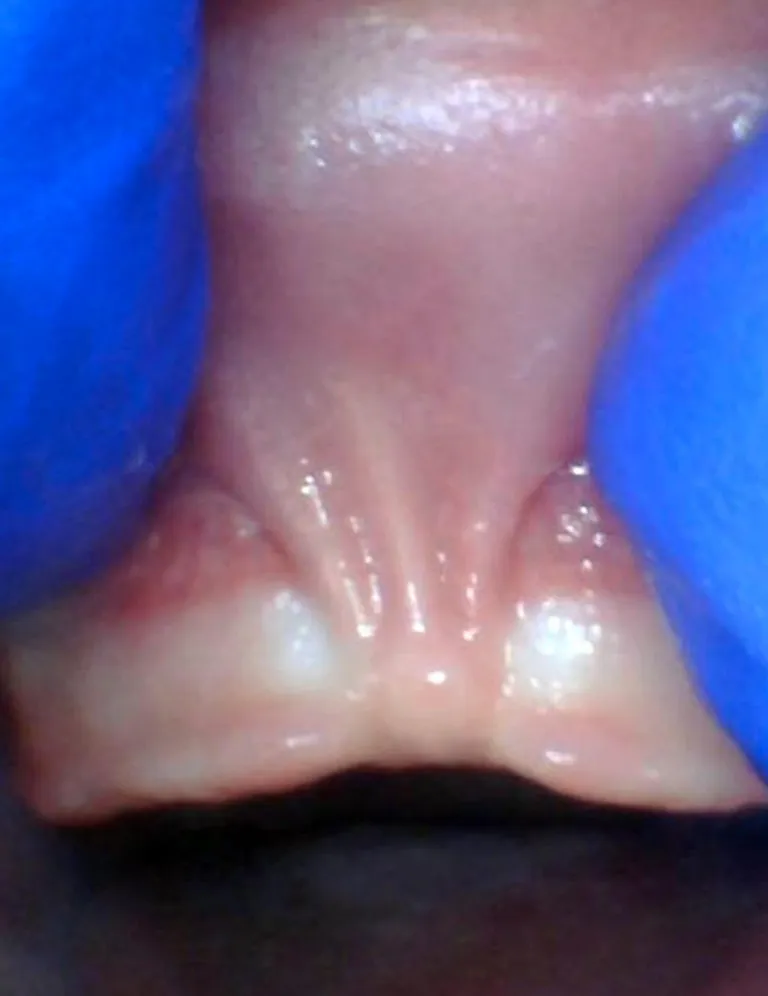

Photos ci-dessous issues du site Tongue-Tie Alabama avec l'accord de R. Baxter.

Bébé - Spectre de restrictions d'un FR labial

Enfant - Spectre de restrictions d'un FR labial